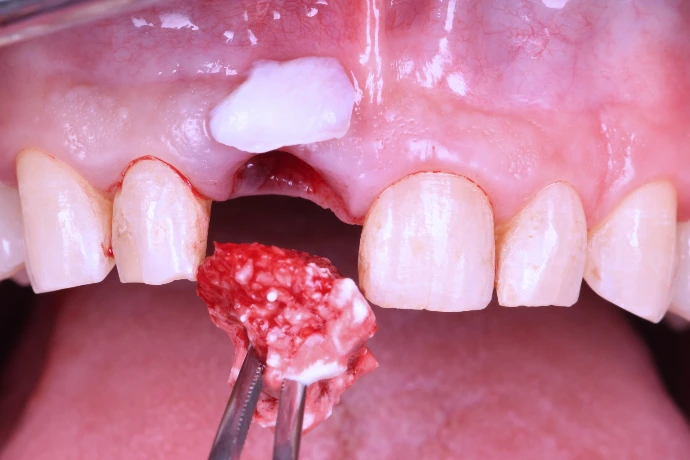

Préservation alvéolaire, régénération osseuse simple et optimisation mucogingivale.

TP : lambeaux, greffes conjonctives et épithélio-conjonctives sur mâchoires animales, ROG péri-implantaire.